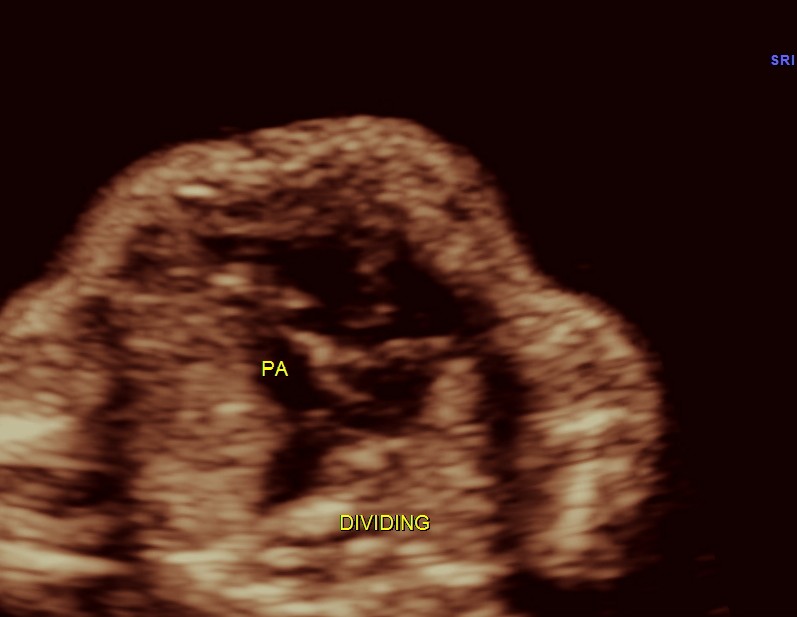

3 vessel view shows a prominent single vessel , which is very suggestive of outflow tract anomalies like transposition of great arteries, double outlet right ventricle , truncus arteriosus and corrected transposition of great arteries.

another view of the above two

here we can see the pulmonary artery with its two branches arising from the lower (left) ventricle .and the aorta arising from the anterior (right ) ventricle.

pulmonary artery dividing into two